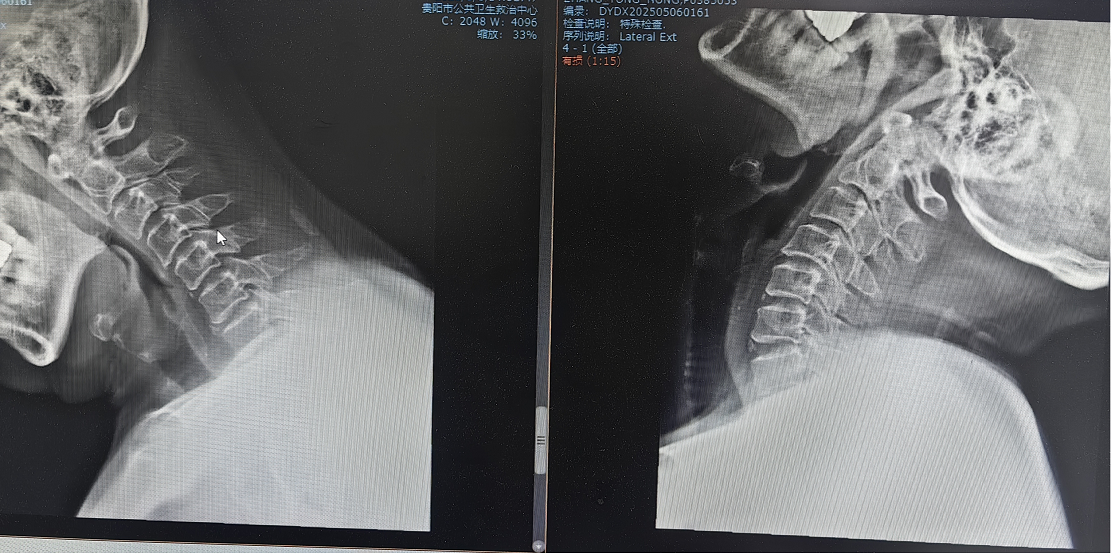

患者因"頭痛、雙上肢麻木伴下肢乏力1月"入院,此前長期保守治療效果不佳,癥狀持續(xù)加重并出現(xiàn)行走不穩(wěn)。經(jīng)多學科聯(lián)合會診,團隊決定采用國際先進的零切跡cage融合術。手術歷時2小時,出血量僅10ml,術后患者即刻感到頸部及肢體癥狀顯著緩解,術后三天即可下床活動,微創(chuàng)切口(3—4厘米)及快速康復效果獲家屬高度贊譽。